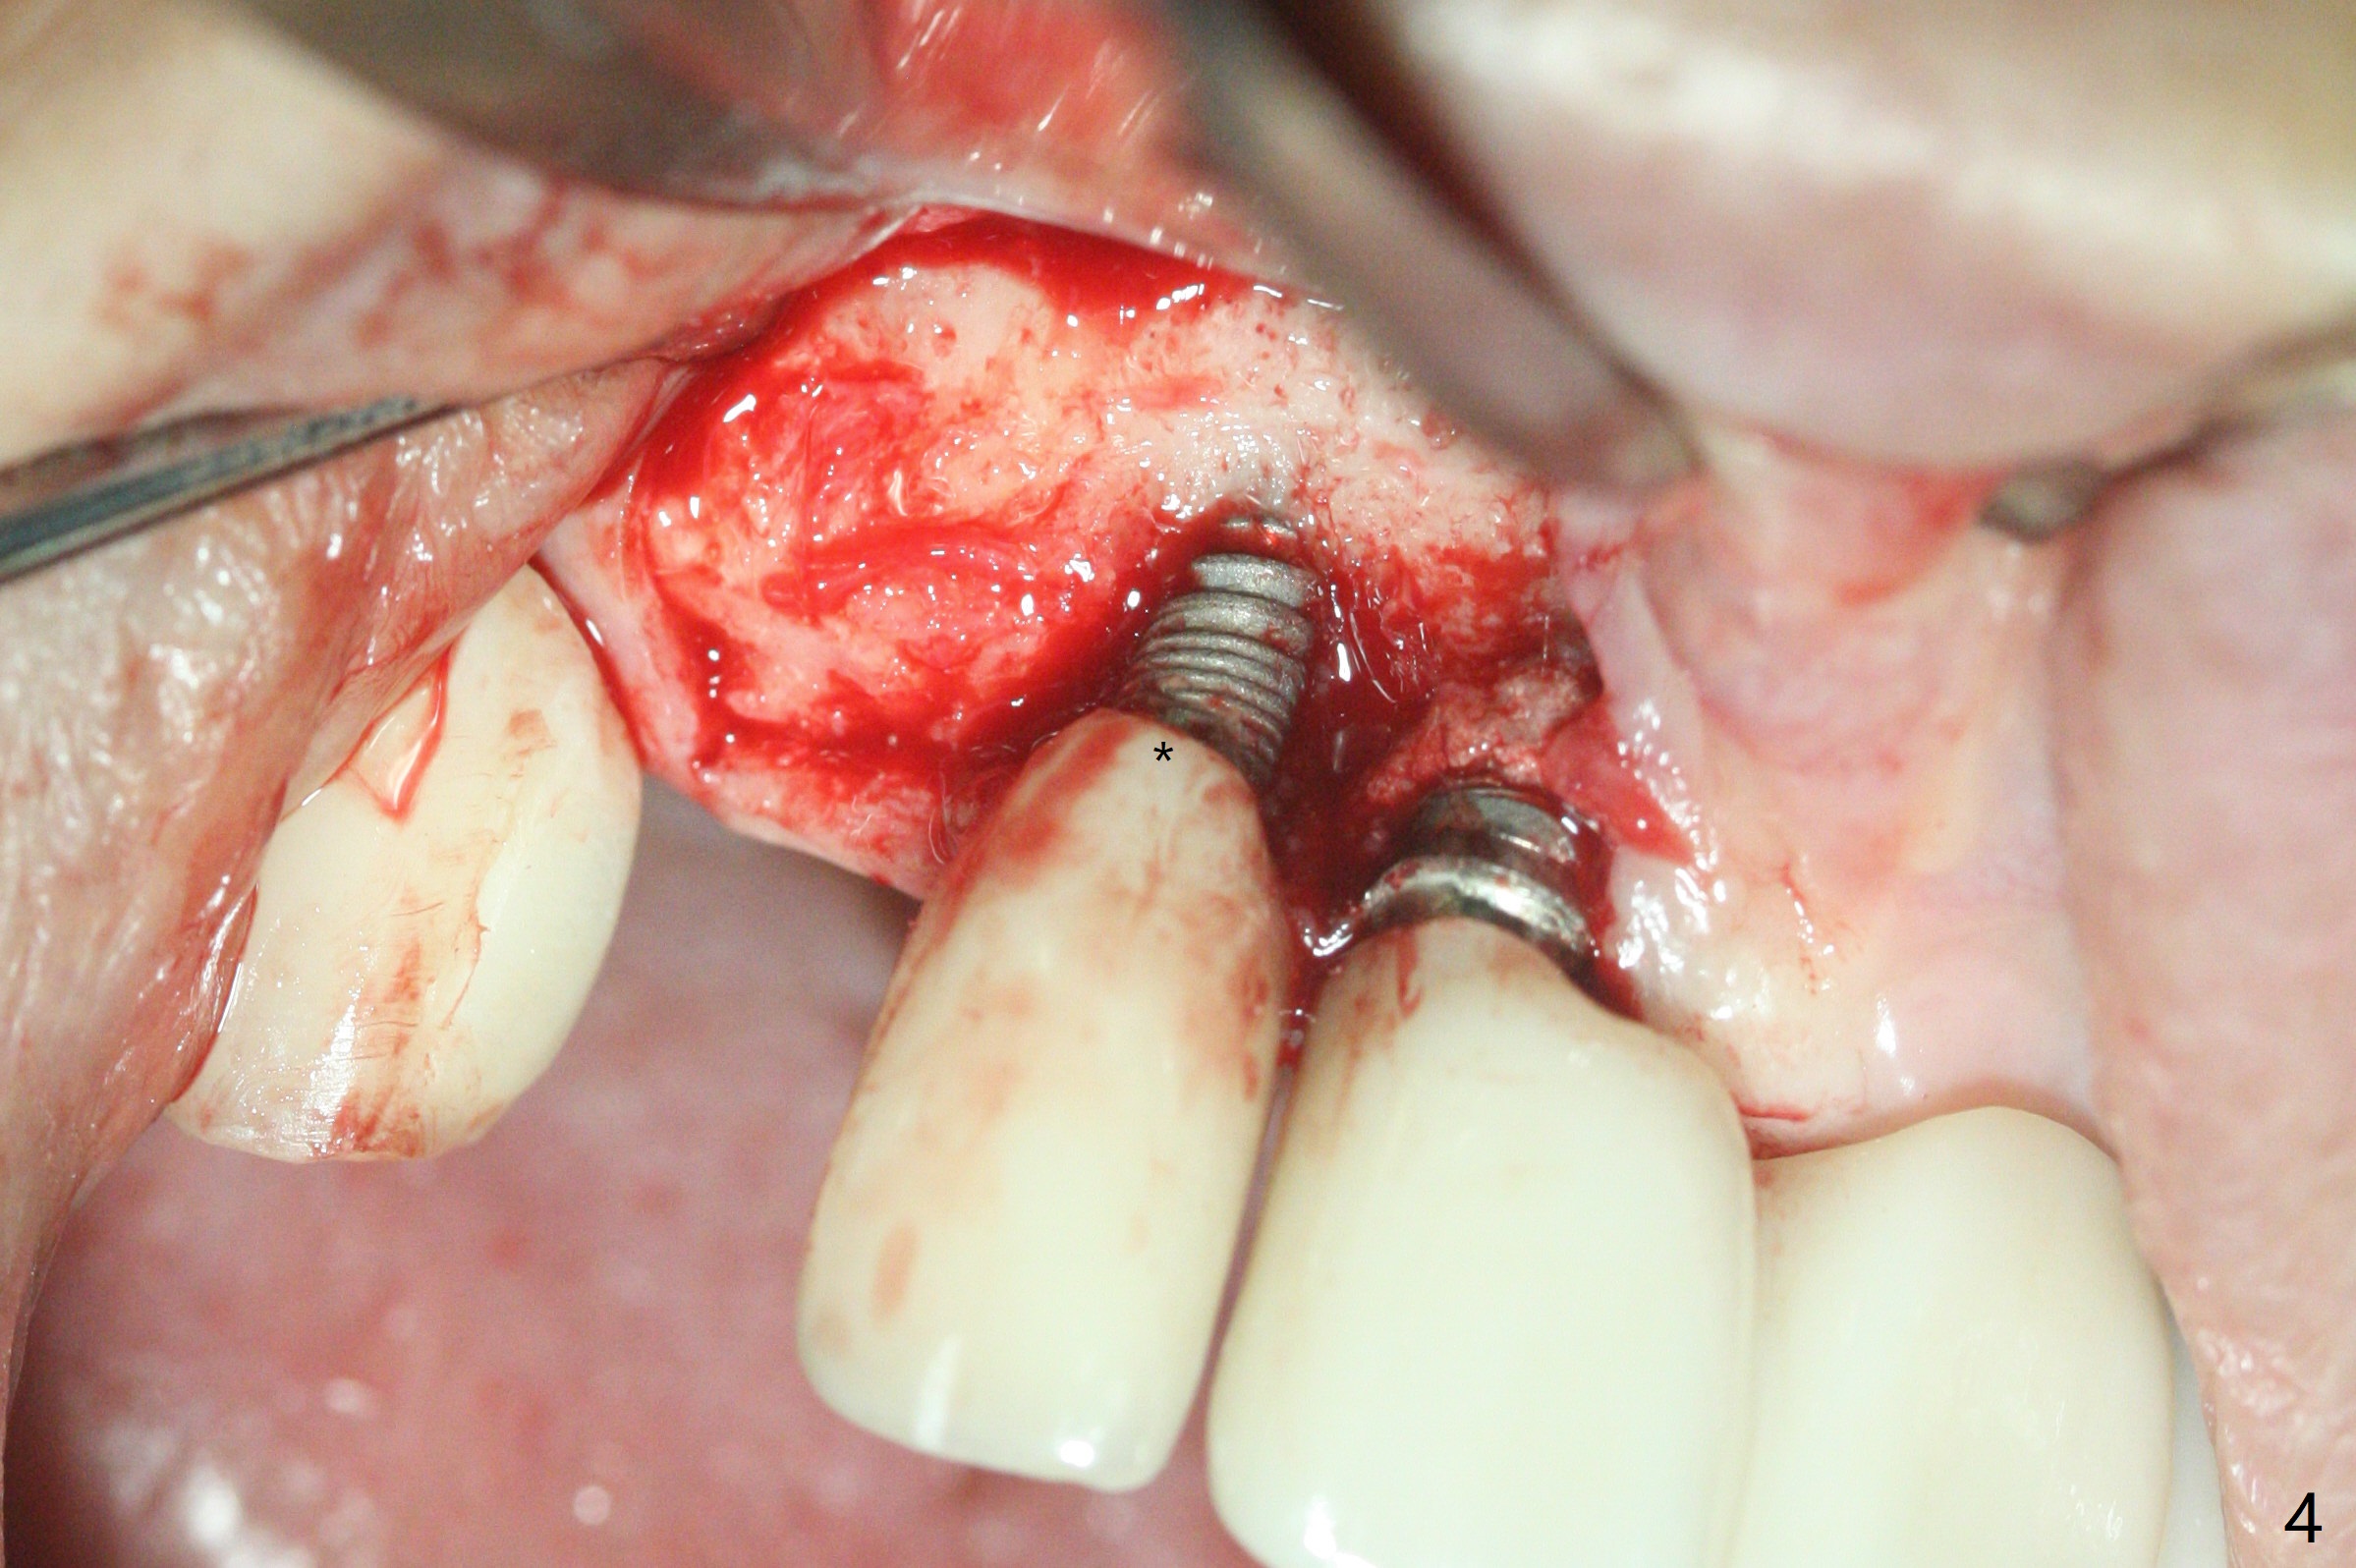

64岁女3-7牙桥,7号牙植体颊侧牙龈缘红肿(图一:*),脓液(图二:^),需要切开清洗,但是6号牙桥墩颊侧非角化龈(N)妨碍切口,所以必须去除桥墩,暴露牙槽嵴顶角化龈(图三:K),容易切开,最后缝合而不容易出血,伤口容易愈合。切开清创后重大发现是牙冠边缘(图四:^)直接接触植体微螺纹,没有基台与牙龈之间形成的屏障,有利于口腔细菌直接感染植体。直感告诉术者必须缩短牙冠边缘,抛光。然后缺损处放置粘性骨粉(图五,八:S,与图七(术前)比较),表面覆盖PRF膜,缝合(图六)。准备术后尽早去除牙冠,预防细菌再次感染。并且在6号牙位植入2x8.5毫米植体。